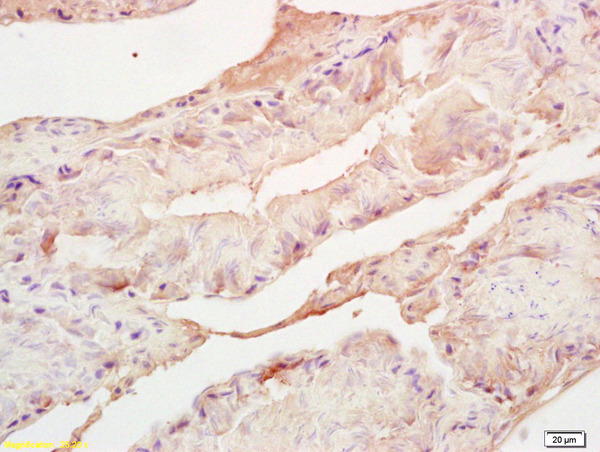

- Main image

- Experimental details

- Formalin-fixed and paraffin embedded mouse testis labeled with Rabbit Anti Adrenodoxin/FDX Polyclonal Antibody, Unconjugated (bs-11426R) at 1:200 followed by conjugation to the secondary antibody and DAB staining

- Sample type

- Mouse

- Other comments

- Testis